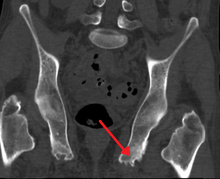

| Enthesopathy of the pelvis likely due to ankylosing spondylitis | |

Enthesopathy of the pelvis likely due to ankylosing spondylitis